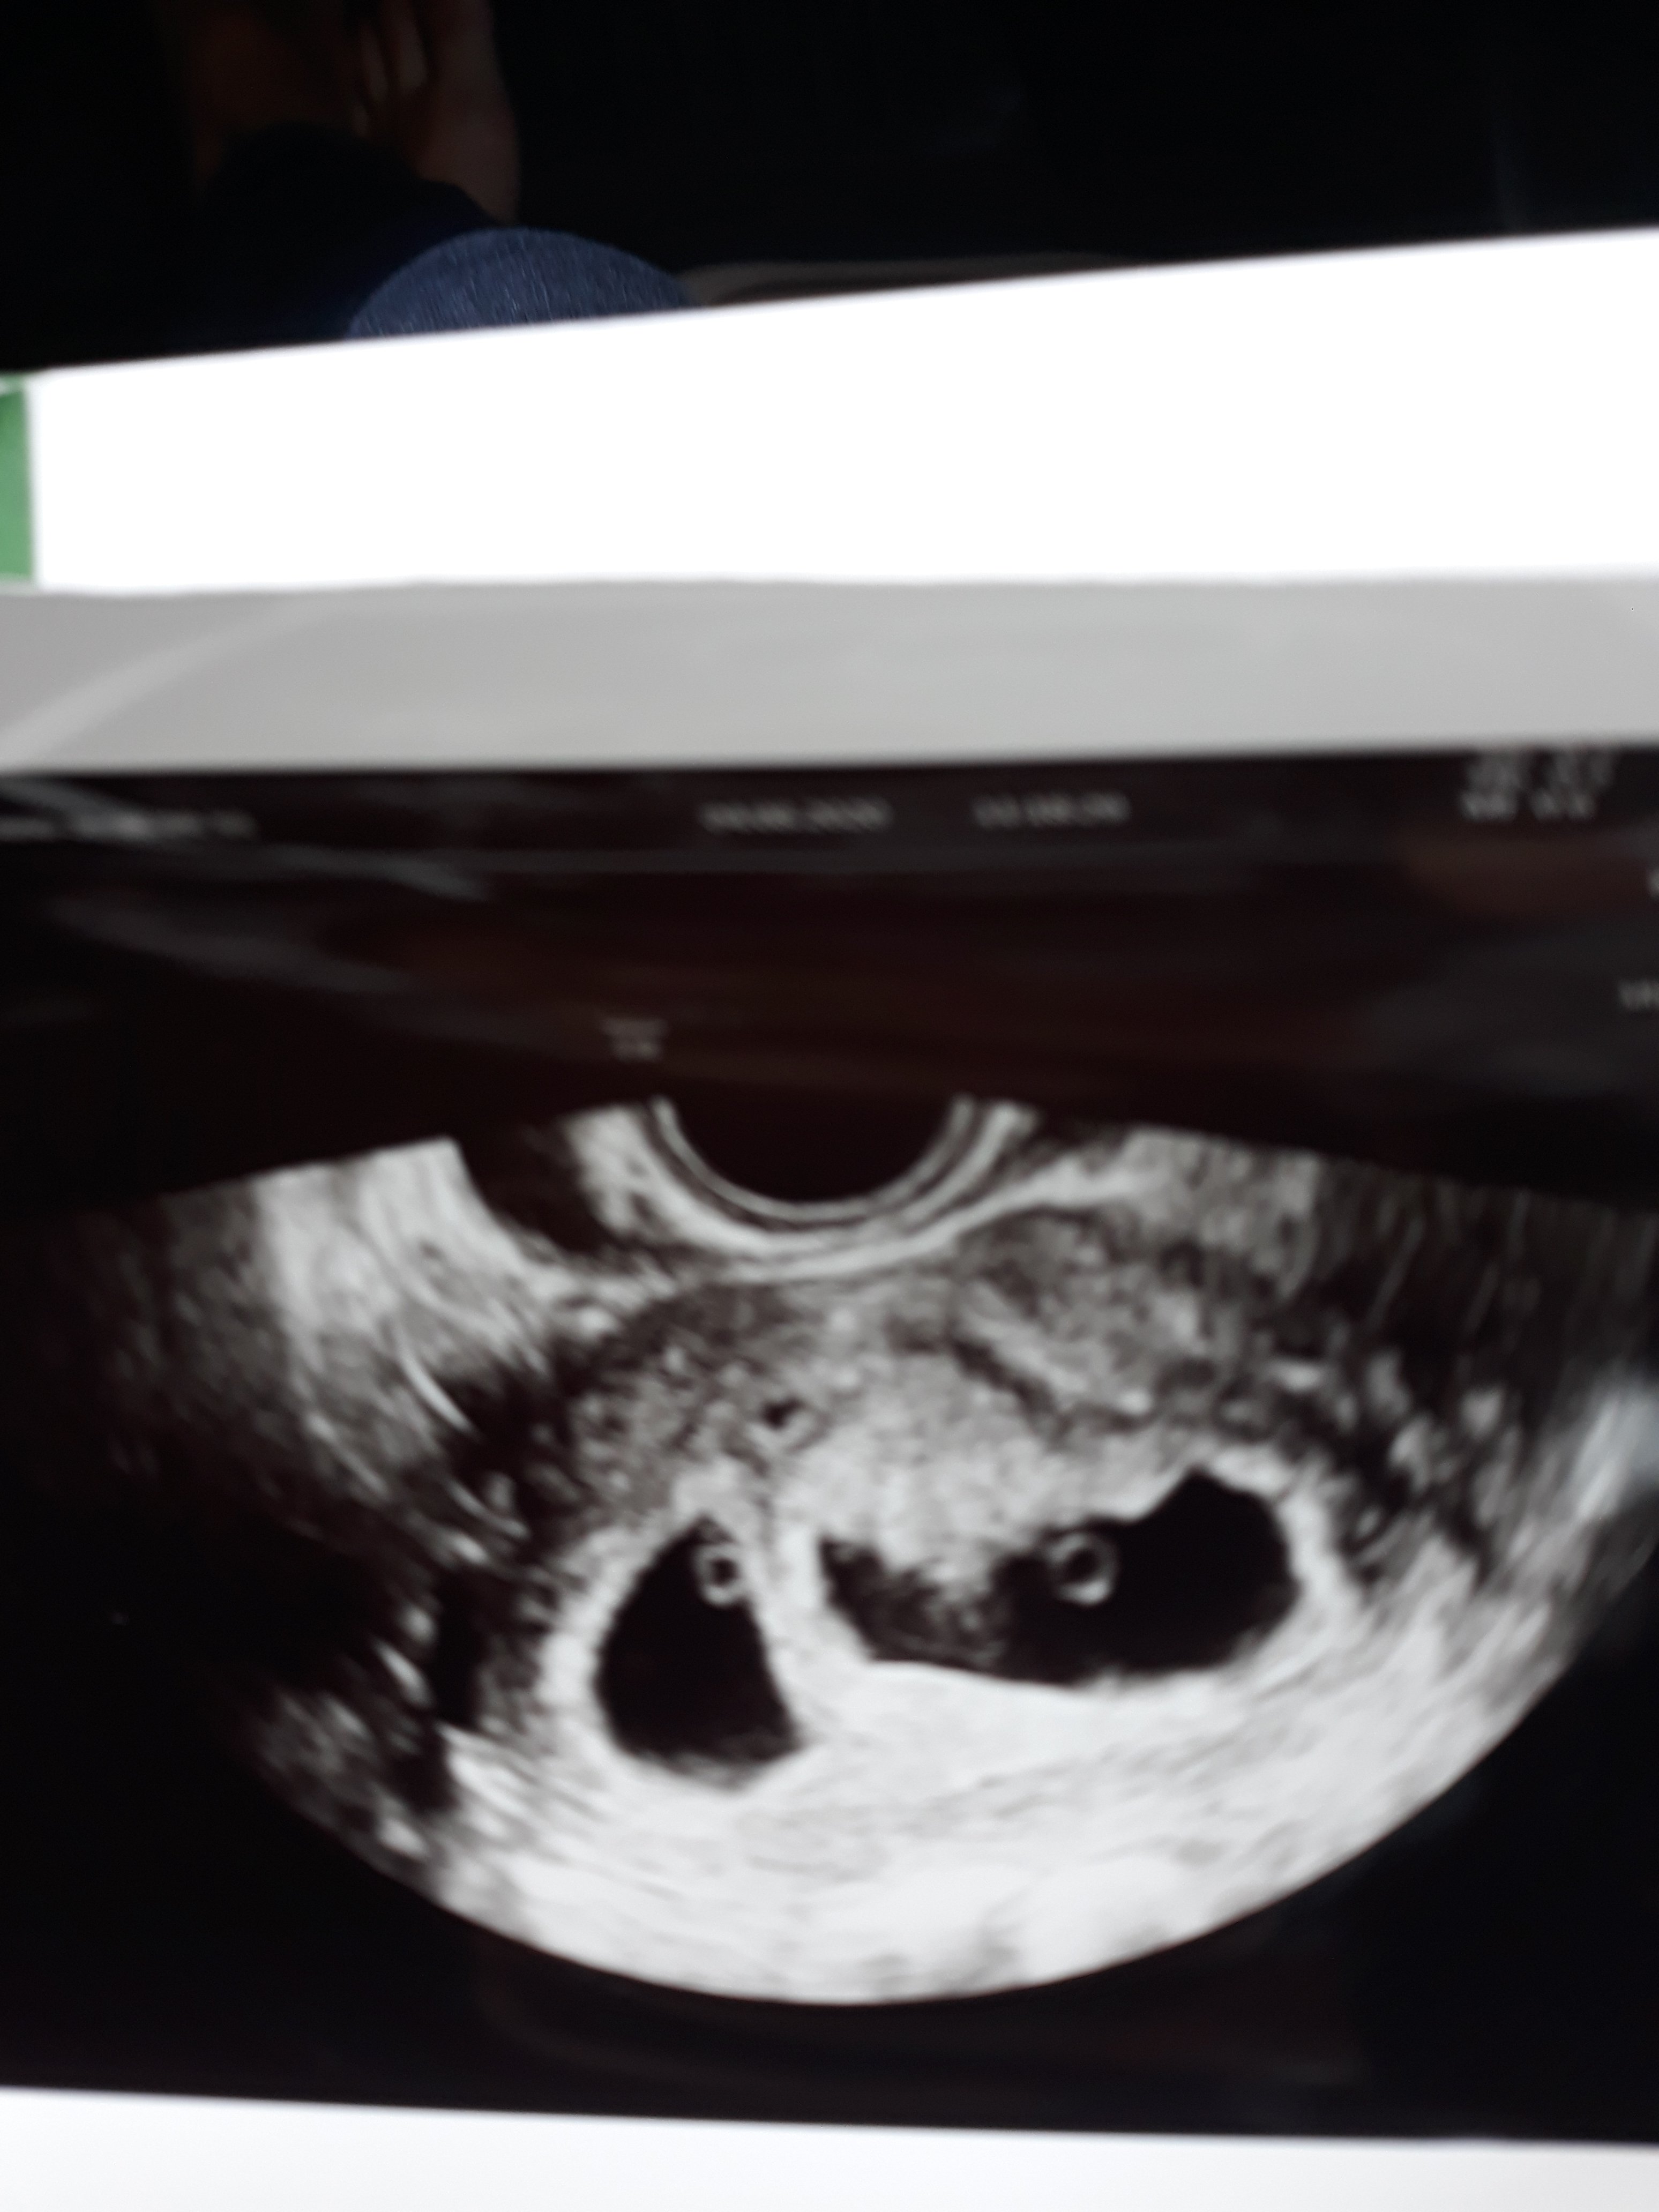

Już gratulowałam, ale napisze tu jeszcze raz:tak się kuwwwwwwwaaaaa cieszę, aż się poryczałamDziewczyny widzialam dwa serduszka. Lekarz powiedział że wszystko jest idealniejeszcze chyba nie wierzę że to się dzieje. Dostalam nawet rwcepte na frexiparyne.na encorton juz nie

Boże co za cudowny widok [emoji3059][emoji3059][emoji3059]Dziewczyny widzialam dwa serduszka. Lekarz powiedział że wszystko jest idealnie [emoji7][emoji7][emoji7][emoji7] jeszcze chyba nie wierzę że to się dzieje. Dostalam nawet rwcepte na frexiparyne.na encorton juz nie[emoji6]